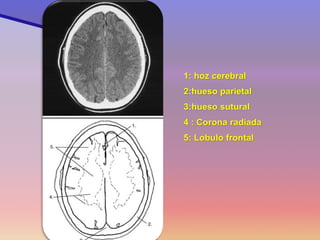

1: hoz cerebral

2:hueso parietal

3:hueso sutural

4 : Corona radiada

5: Lobulo frontal

Corte 10

1: hoz cerebral 2:hueso parietal 3:hueso sutural 4 : Corona radiada 5: Lobulo frontal Corte 10